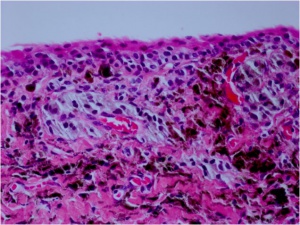

A PAM (Fig. 2B) without atypia is best characterized by minimal melanocytic hyperplasia along the basal epithelial layer of the conjunctival. PAM with atypia shows usually isolated or confluent nests of atypical melanocytes. Pagetoid spread can also be observed. The melanocytes exhibit varying signs of atypia as large abnormal cells, prominent nucleoli, a high nuclear-cytoplasmic ratio, and mitotic figures.

A conjunctival malignant melanoma shows invasion of melanoma cells into the subepithelial layers. The cells exhibit the above named signs of atypia. Remnants of PAM or nevus may be found in or contiguous to the melanoma.